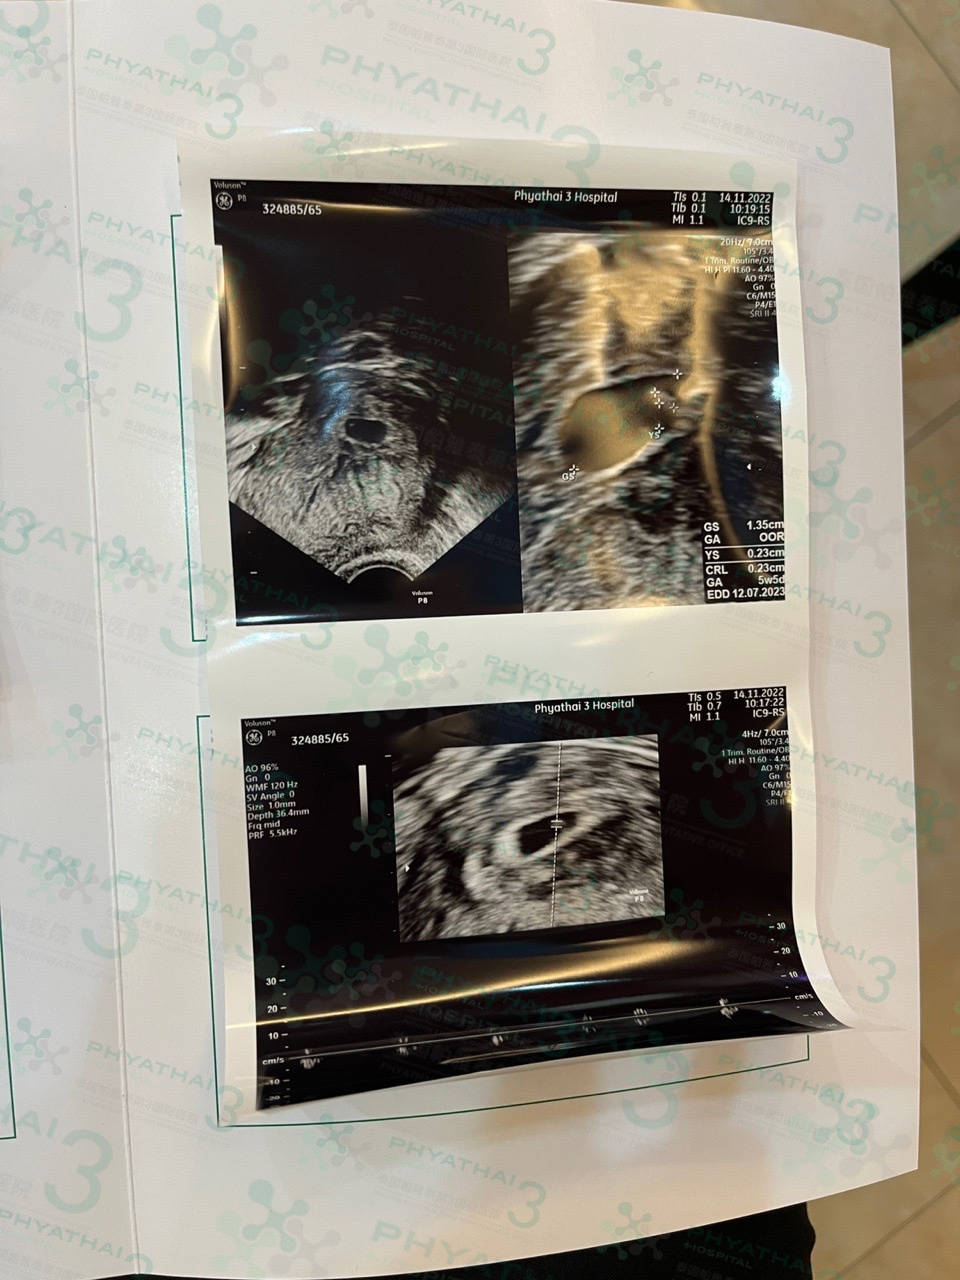

今天见诊患者刚好孕期六周 到了看孕囊的周期 看到了宝宝的卵黄囊和小胎心了 孕期还小宝宝也是还很小所以在每个孕期时间要做孕检